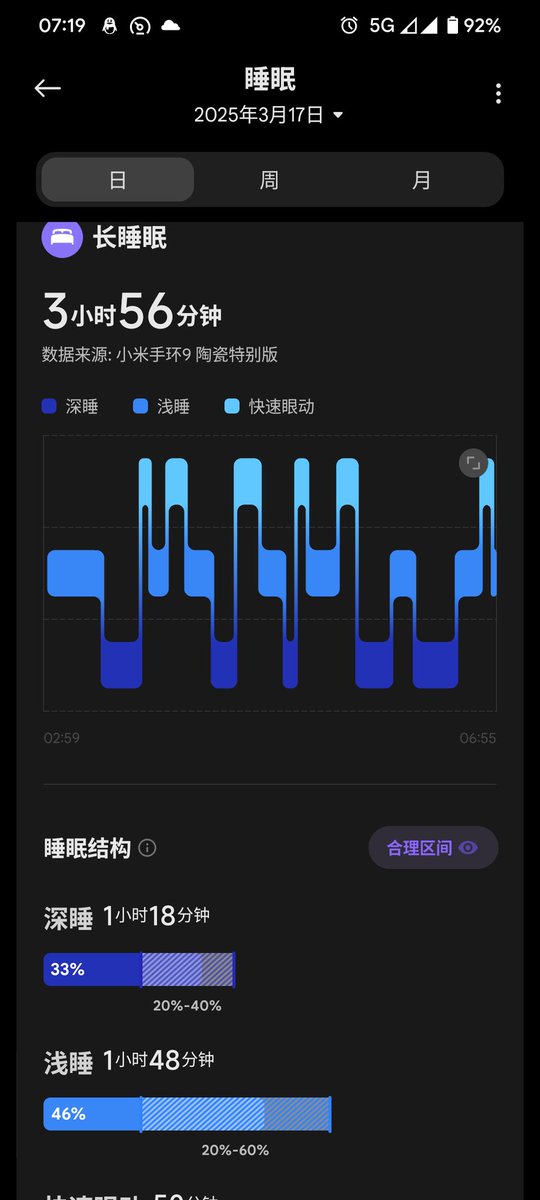

甚至在第二天有余晖的感觉,虽然发生了很多破事但没怎么影响心情*抗焦虑&镇静

此剂量下对睡眠的改善作用,增加了慢波睡眠且没有影响rem,精力恢复+